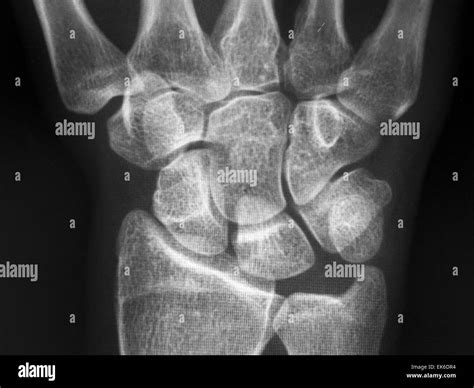

Interpreting the results of a Wrist Bones Xray requires the expertise of a radiologist or orthopedic specialist. The images will be reviewed to identify any abnormalities or injuries. Some common findings on a wrist X-ray include:

• Fractures: Visible breaks or cracks in the bones.

• Dislocations: Misalignment of the bones in the wrist joint.

• Arthritis: Degenerative changes in the joints, such as narrowing of the joint space or bone spurs.